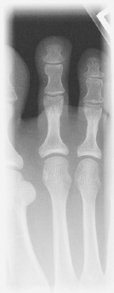

Alternative routine may include entire foot on AP toe projection for possible secondary trauma to other parts of foot (see AP foot).

• Patient prone with foot and great toe carefully dorsiflexed so the plantar surface forms a 15°–20° angle from vertical if possible (adjust CR angle as needed)

This may be a more tolerable position for patient to maintain if in great pain.